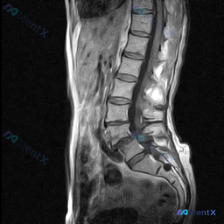

整理了一份网上看到的腰椎MRI病例资料,标注里直接提了“Scoliosis”(脊柱侧弯),但仔细看提供的只有矢状位T2序列。 先把影像核心发现列出来: 1. 椎间盘:各腰椎间盘T2信号普遍减低(黑盘征),提示退变;L4/L5、L5/S1椎间盘后缘明显突出,L5/S1还有向下脱出移位 2. 椎管与神经...

整理到一份影像分析的病例资料,觉得阅片逻辑里有几个坑特别值得拿出来讨论。 资料背景是:患者那边的关注点是「脊柱侧弯」,但目前只拿到了腰椎MRI T2序列矢状位的图像。 先不说侧弯,先放一下这份MRI里明确看到的影像表现: - L1/L2到L3/L4椎间盘信号还行; - L4/L5、L5/S1 是重灾...

最近看到一份腰椎MRI的描述,觉得挺有警示意义,整理一下思路和大家讨论。 病例核心影像信息 - 关键征象:L4-5椎间盘水平,下缘可见中央及右侧旁中央高信号病灶,且与椎间盘直接相通 - 其他影像表现:L4-5椎间盘后缘弥漫性、对称性信号降低(退变脱水);椎间盘后缘广泛性膨出伴局灶性后正中偏右侧突出;...